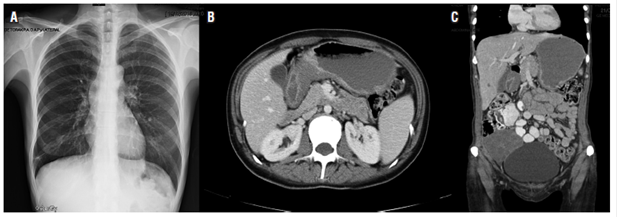

The oncology department evaluated these results and chemotherapy was started with 1.5 g of capecitabine administered orally every 12 hours from July 7, 2015 for 14 days plus a single 125 mg dose of cisplatin administered intravenously. She completed 8 cycles. Significant clinical relief was detected at periodic follow-up appointments. The patient recovered her functional and nutritional status and numbers for biochemical markers such as ACE, CA 19-9 and CA-125 improved. Ascites disappeared and the ovarian mass stopped growing. Another laparoscopy on November 12, 2015 found an ICP of 8, with no peritoneal implants in diaphragmatic domes, a mobile stomach without adhesions and metastatic compromise of the right ovary. There was no free fluid in the abdominal cavity (Figure 2).

Figure 2 A. Normal chest radiograph. B. Tomography with thickening of the stomach-body walls. C. Right adnexal mass.